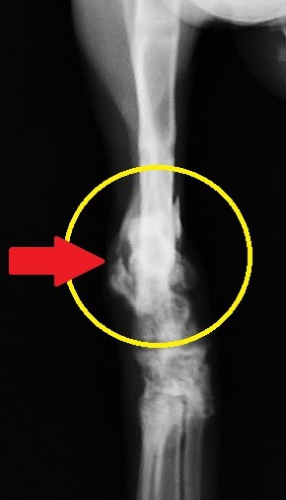

レントゲン検査では脛骨骨折と同時に上腕骨骨折が確認されました。脛骨の骨折部分には写真では見えにくいですが3つの骨折面があり、大小2つの骨片(骨の破片:緑マーカーの間)を伴って割れています。こういった骨が砕けたような骨折を分類上、粉砕骨折と呼びます。この例ではさらに骨折端(オレンジ矢印)が皮膚を突き破って一部外に出ていますので、複雑骨折(開放骨折)の状態です。

というわけで、今回の脛骨骨折は骨が外に出ている開放骨折、折れた骨がバラバラになっている複合骨折(粉砕骨折)、さらに骨折の場所が遠位端(骨の体から遠い端っこ)と、骨折手術のやり難さと治り難さの悪条件が3拍子揃っていました。こういった場合には創外固定が唯一の選択法になるのではないでしょうか。

下のレントゲン写真は手術8か月目のものです。通常の単純な骨折ならば既に完治している期間です。骨折は冬でしたが、固定を外すのが夏になってしまいました。ほぼ同時に手術したもう一か所の上腕骨骨折はプレートによる内固定で手術2か月弱で治療を終えていることを考えると非常に長い治療期間でした。

長期間かけてようやく少しづつ仮骨形成(骨がくっつき始めること)し始めましたので、レジンを除去して5本あった金属ピンを3本に減らした写真です。こうすることで徐々に骨に負荷をかけていきます。